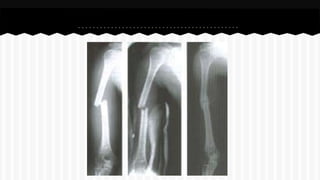

RESPONDA O NOME DO OSSO EM QUE

SE ENCONTRA A (S) FRATURA (A).